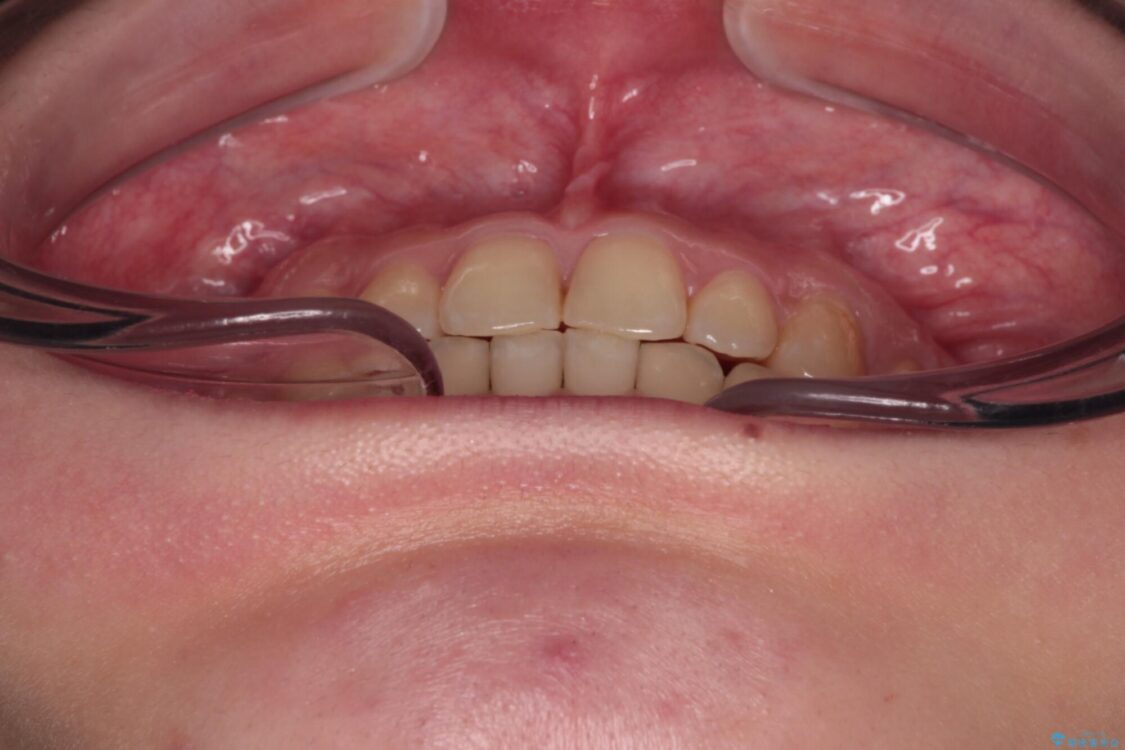

治療前

• 治療途中の奥歯と矯正治療の後戻り インビザライン・ライトによる矯正治療 治療前画像